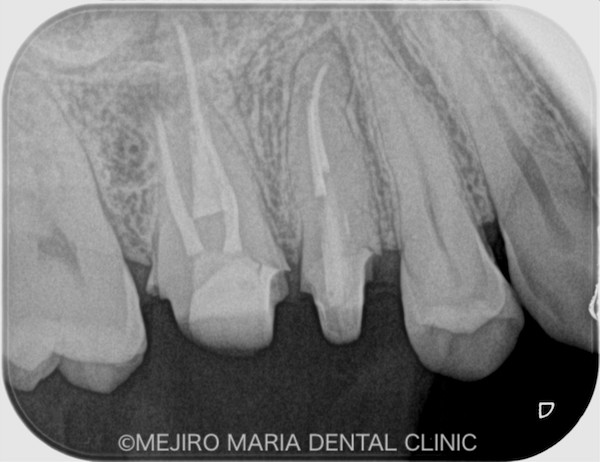

患者様は、「数年前に虫歯治療した歯の、根元が腫れた」という主訴で来院されました。かかりつけ医に相談したところ、痛くないのであれば様子を見るようにと指示されましたが、不安を抱いて当院へお越しになりました。

右上の歯を確認したとろ、当該部位にはフィステル(瘻孔)が確認でき、フィステルより造影してみると、右上6番の歯の根尖部付近から、排膿されていることがわかりました(写真の赤矢印)。フィステル以外に痛みなどの所見は見当たらないものの、「根尖性歯周炎」と診断し、治療を開始しました。